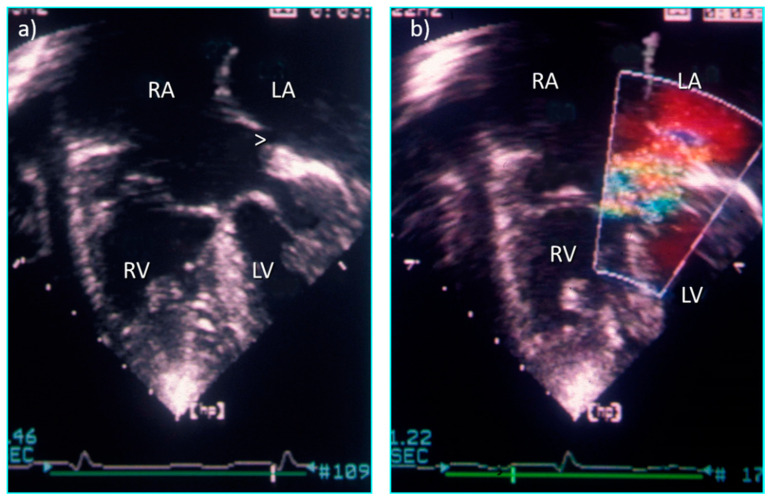

Consider the hypothetical situation of a paediatric cardiologist who, on the basis of a cross-sectional echocardiogram, informs a cardiac surgeon about a patient with a primum atrial septal defect that requires routine repair, and the surgeon takes the patient to the operating room without carefully reviewing and discussing any investigations. For a simple primum defect, no doubt the outcome would be very good because, simply on the basis of the name, the surgeon would anticipate correctly the operative findings. But just imagine the likely consequence if in addition to the primum defect there had been double outlet right atrium, a small and restrictive primum defect with left atrial hypertension, double orifice left atrioventricular valve and left ventricular outflow tract obstruction (Figure 15) caused by anomalous chords from the superior bridging leaflet to the ventricular septum. The patient would have been much more likely to survive the operation or have a perfect outcome of repair had the surgeon undertaken a complete review of all the investigations and completely understood the data. But giving the cardiac malformation a ‘label’ is unlikely materially to improve outcome further if the cardiac surgeon was unable to interpret echocardiographic or magnetic resonance images and relied entirely on verbal or written descriptions of any anomalies and observations at the time of surgery.

Figure 15.

Four chamber echocardiographic sections from a heart with double outlet right atrium and restrictive primum defect (ASD) (a) without colour flow Doppler and (b) with turbulence across the restrictive ASD.